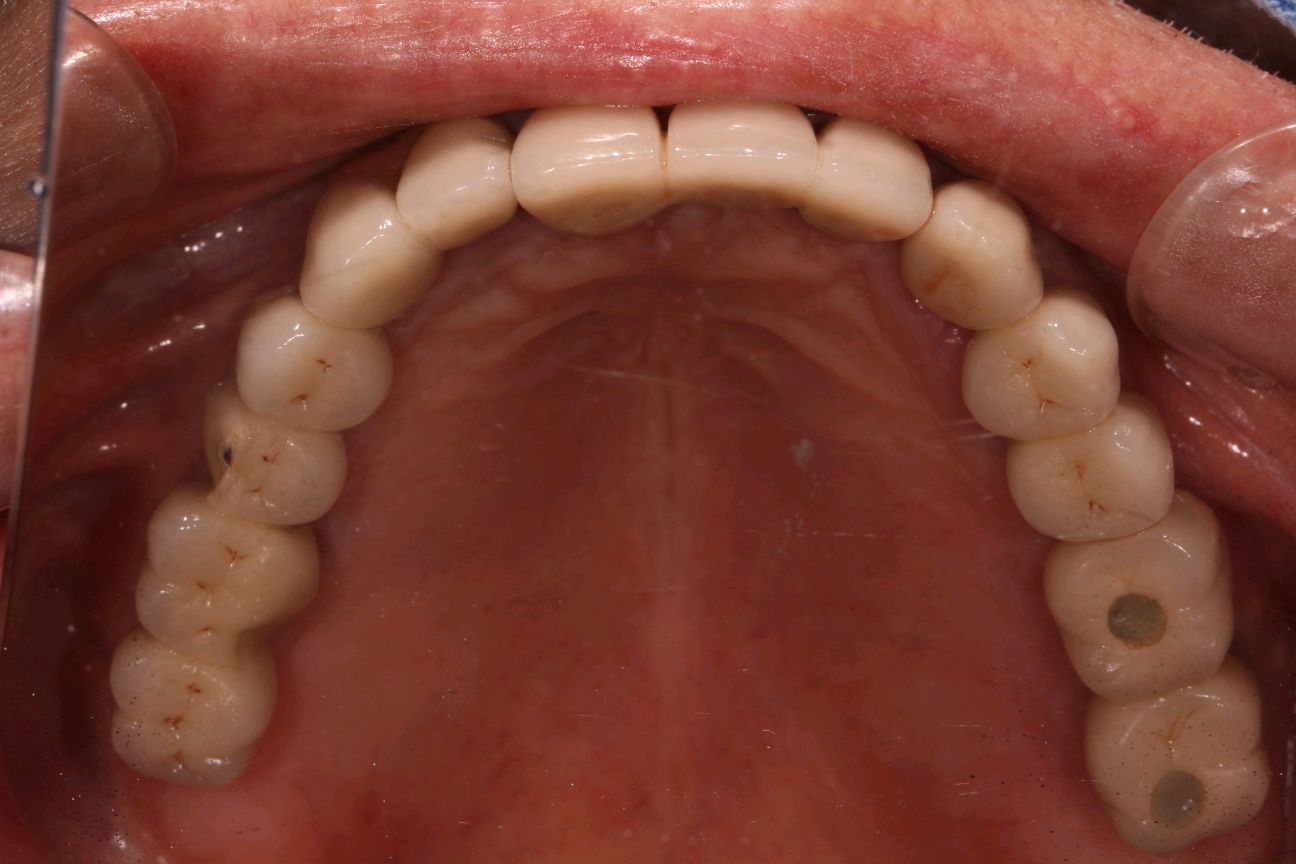

程先生,80岁种植牙复诊,共种了17颗牙,距离第一颗种植牙己定期随访15年,无松动疼痛等症状,用的很是满意。

本次复诊进行了OHI口腔卫生宣教,刷牙、牙线、间隙刷使用宣教和全口超声波洁治,喷砂洁治,抛光,上药,并愉快的约了明年今日复诊。